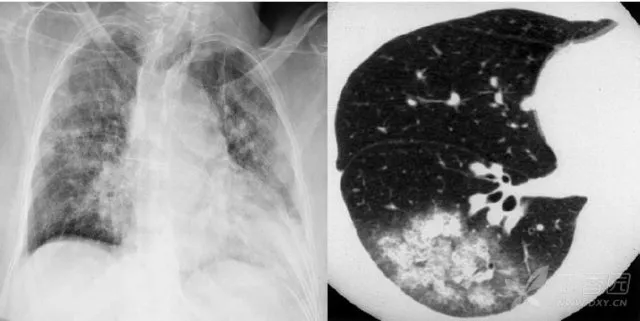

大葉性肺炎胸部影像

簡(jiǎn)單來講,肺炎出現(xiàn)較大的病灶,局限在一個(gè)肺葉,就叫大葉性肺炎。大葉性肺炎也叫肺泡性肺炎,這是因?yàn)榇笕~性肺炎的炎性滲出主要發(fā)生在肺泡。細(xì)菌、病毒、真菌、以及肺炎支原體等非典型病原體都可以引起大葉性肺炎。